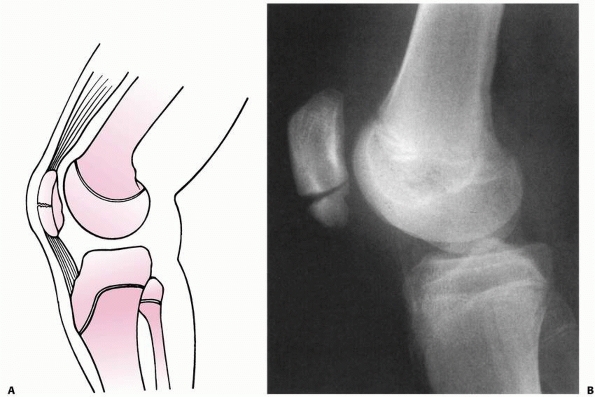

the knee joint (Fig. 23-3A). However, loading

to failure across the immature knee is more likely to lead to physeal

failure due to tensile stresses that are transmitted through the

ligaments to the adjacent physis (Fig. 23-3B).45

FIGURE 23-3 A. In a skeletally mature patient with closed physis, tensile failure usually occurs across the ligament. B.

In a skeletally immature patient with open physis, failure usually occurs across the physis. (Reprinted with permission from Skaggs DL, Flynn JF. Trauma about the knee, tibia, and foot. In Skaggs DL, Flynn JF, eds. Staying out of Trouble in Pediatric Orthopaedics. Philadelphia: Lippincott Williams & Wilkins; 2006.) |